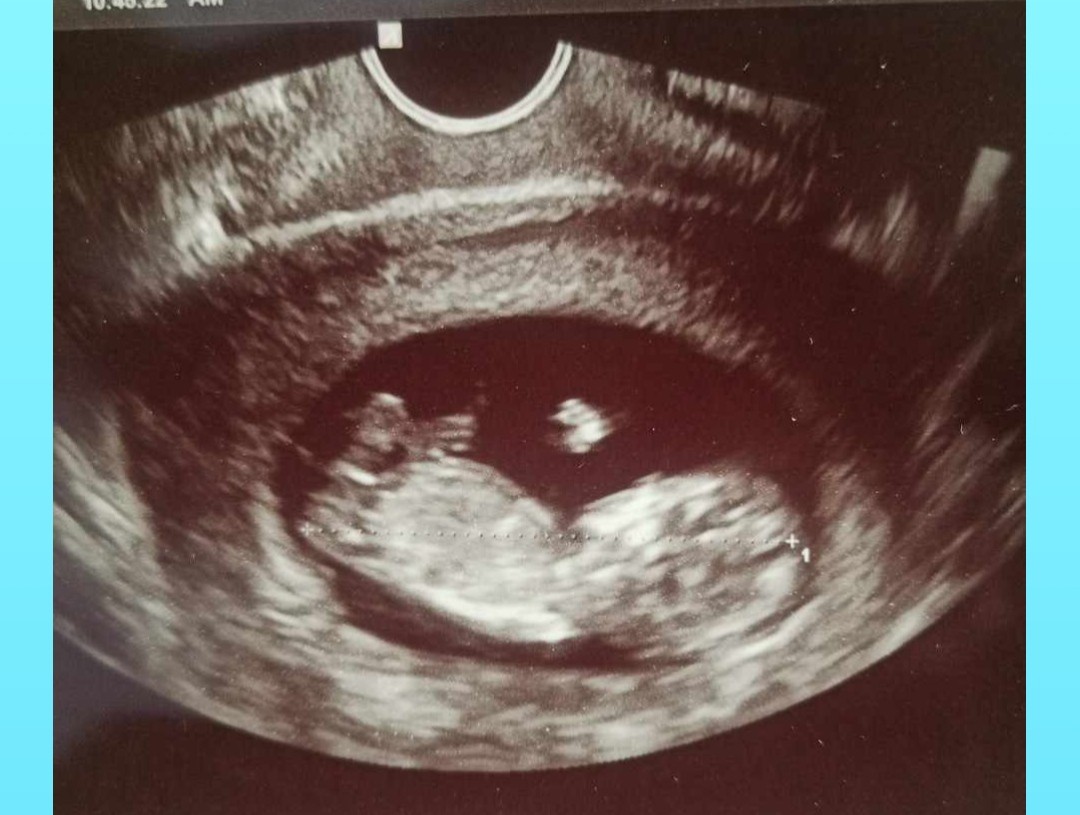

Który tydzień?Witam serdecznie, czy widać na tych Usg płeć dziecka ?

12+4Który tydzień?

11+6 to za wczesnie na ocenę wyrostka płciowegoDzień dobry. Czy na tych zdjęciach widać już płeć? Jak myślicie ?![]()